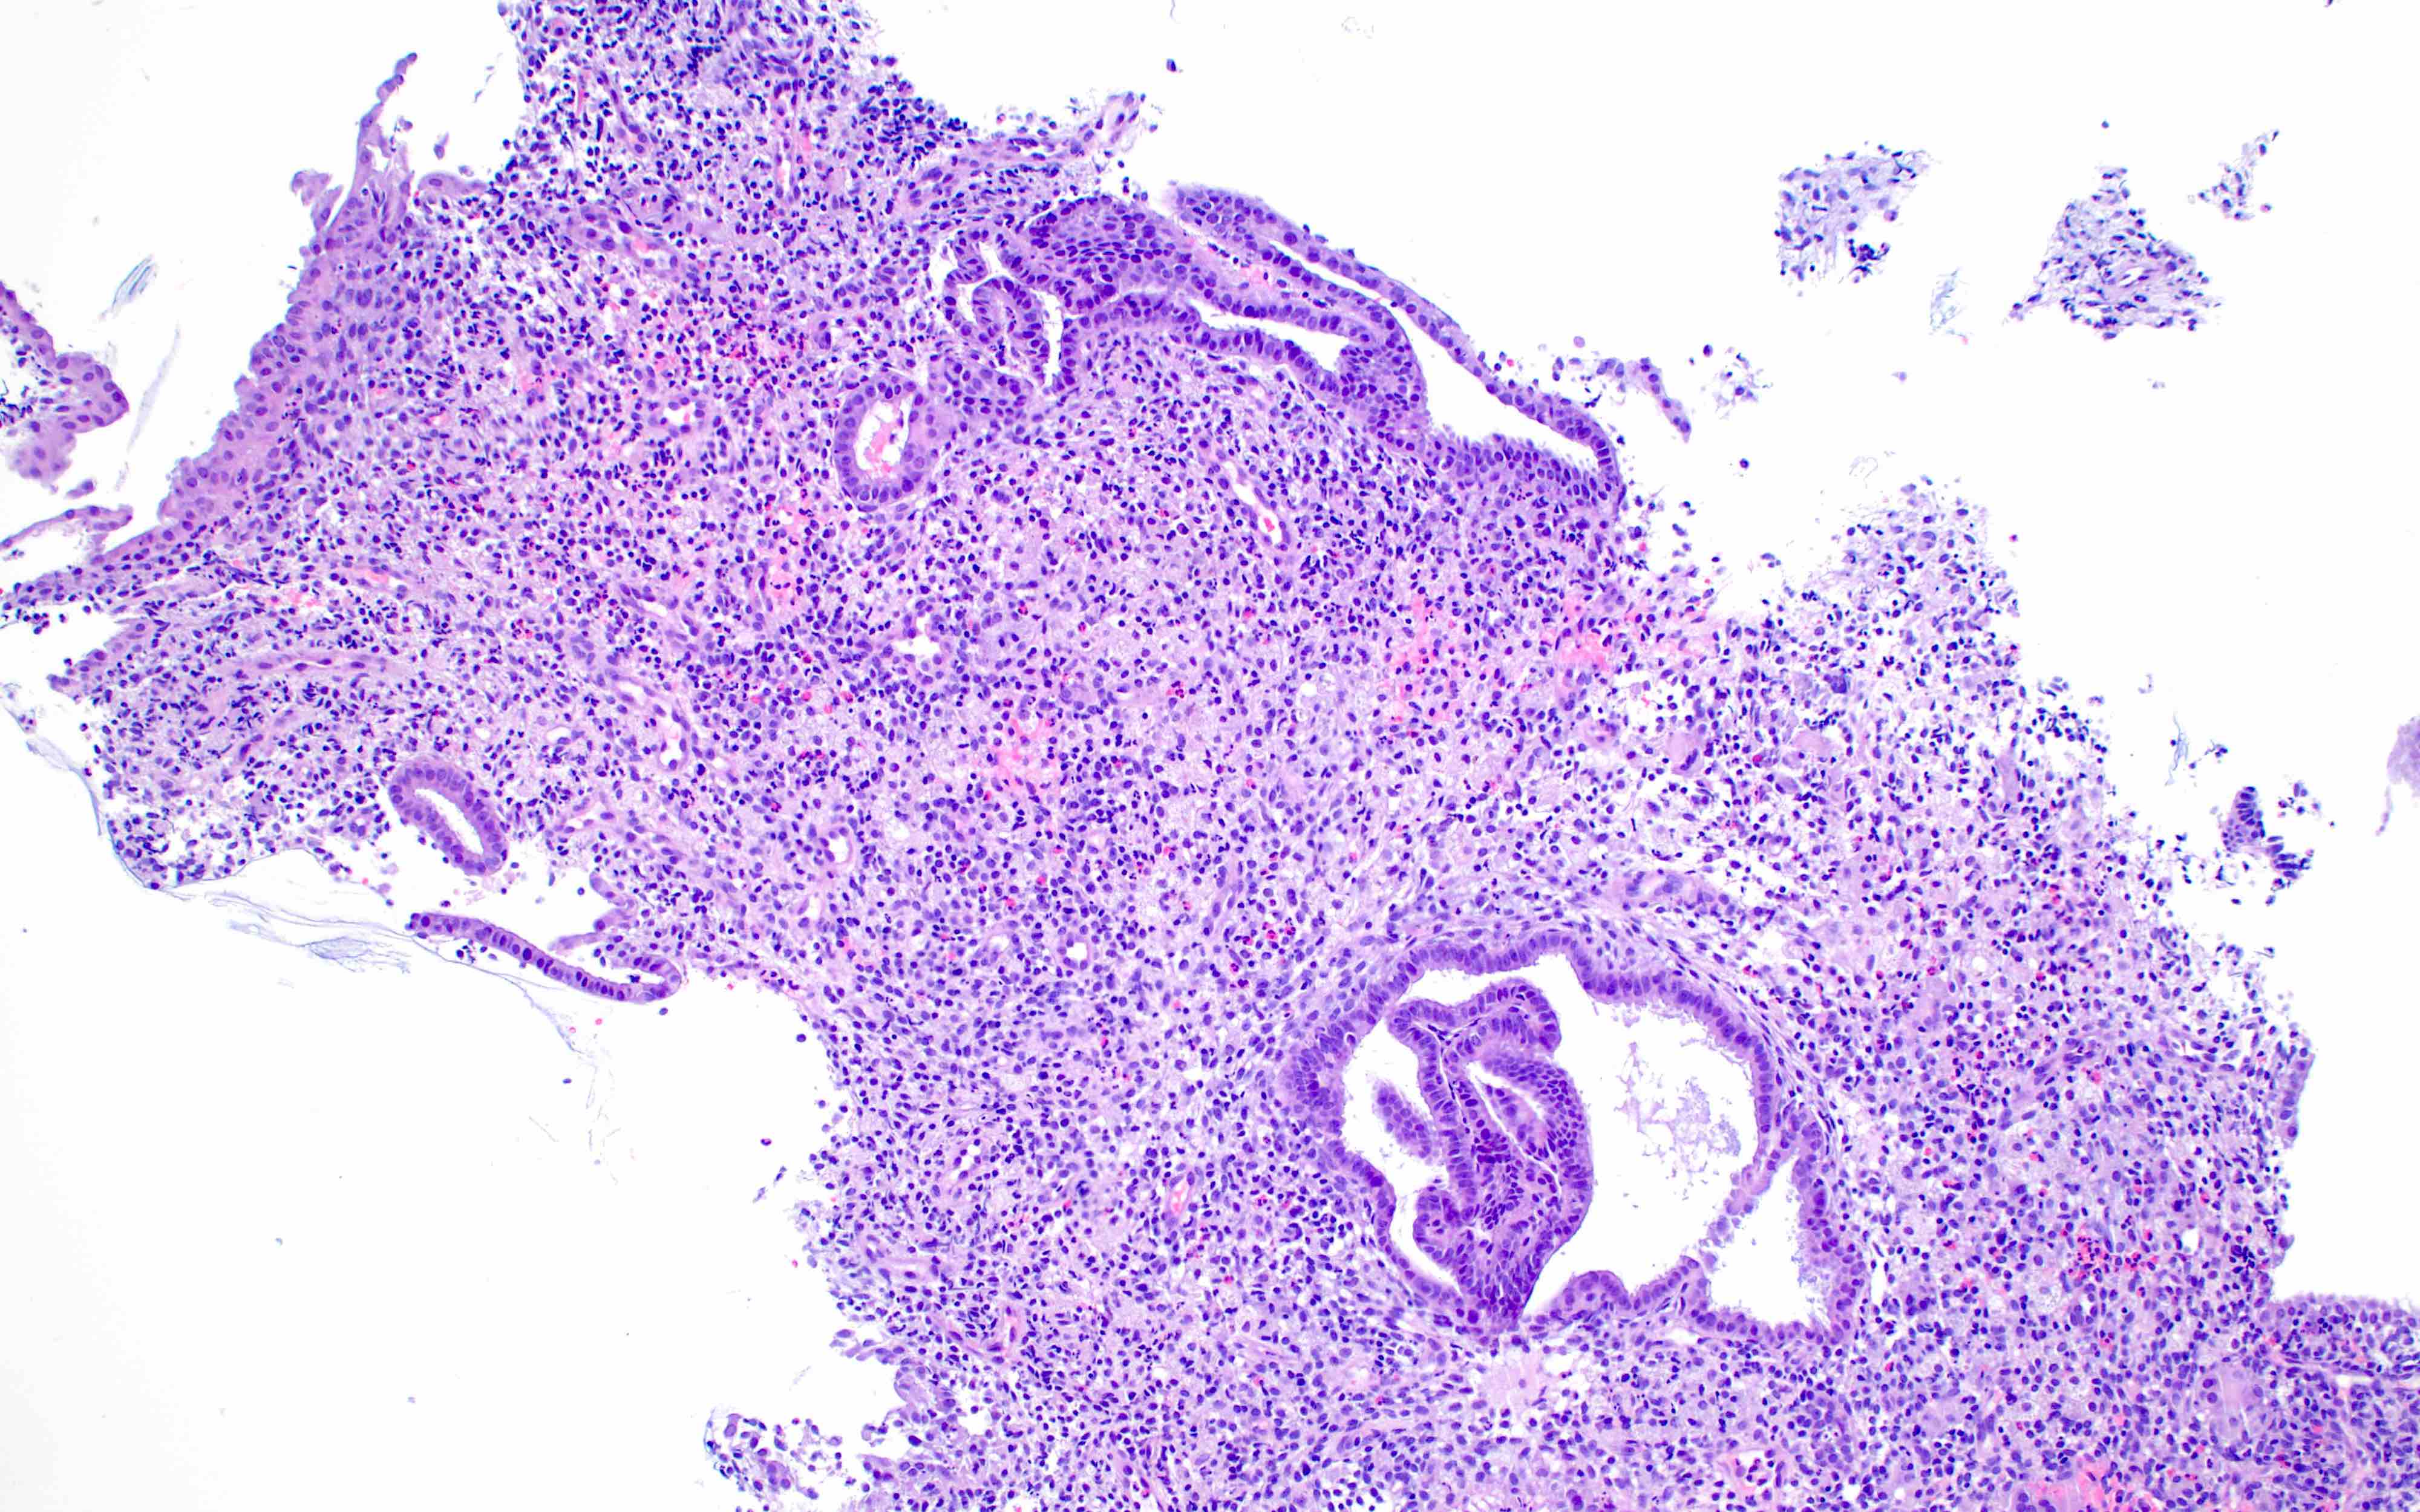

Microscopic (histologic) images

Contributed by Stephanie L. Skala, M.D. and Yuri Tachibana, M.D.

Chronic endometritis

Xanthogranulomatous endometritis

- Chronic endometritis

- Plasma cells (required) with or without lymphoid follicles

- Spindled stromal cells

- Acute endometritis

- Neutrophils infiltrating and destroying endometrial epithelium

- Neutrophils filling gland lumina

- With or without microabscess formation